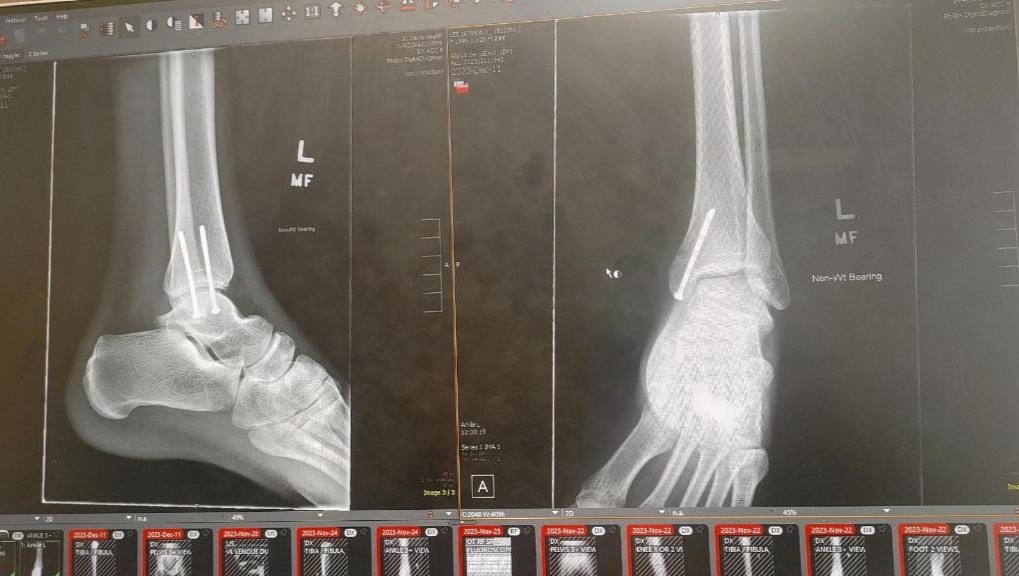

Support Our Dedicated Employee, Desmond, in his Car Accident Recovery! We are reaching out to you in a time of great need for our beloved employee, Desmond. Desmond has been an invaluable member of our team at 3D Detail for the past three years, consistently bringing his remarkable skills, dedication, and positivity to our workplace each day. Unfortunately, Desmond has recently experienced a devastating car accident that has left him with severe injuries and significant financial challenges. As a result, he is unable to work and faces a long road to recovery both physically and financially. We have created this GoFundMe campaign to rally around Desmond and offer our support during this difficult time. Our primary objective is to raise $15,000 to assist Desmond in covering his immediate medical expenses, ongoing treatments, and provide some financial stability as he navigates this challenging journey. Desmond's unwavering commitment to providing exceptional service to our clients has always impressed us. Now, it's our turn to demonstrate our gratitude and support for him. Your contribution, regardless of its size, will go a long way in making a positive impact on Desmond's well-being and ease the burden he currently faces. We appreciate every ounce of assistance, and we firmly believe that with your help, Desmond will get through this challenging chapter and embrace a brighter future.